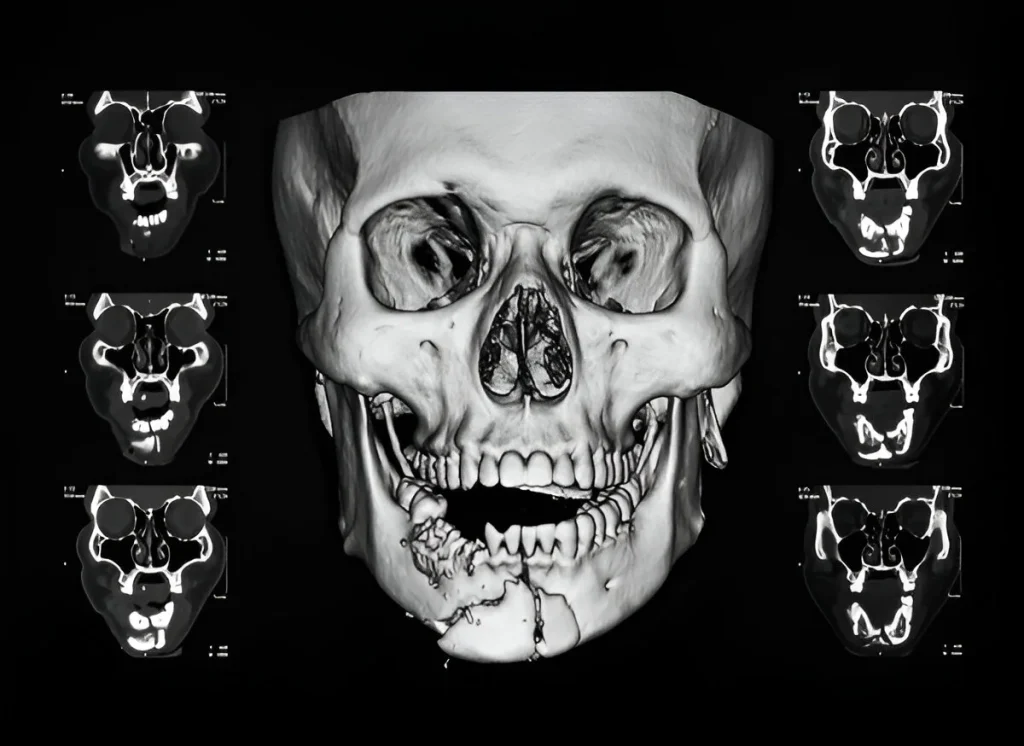

CT Facial Bones in Navi Mumbai | Henotic Diagnostics

Looking for a CT Facial Bones scan in Kharghar? At Henotic Diagnostics, Kharghar, we provide advanced CT imaging with high precision. Because facial bone injuries and sinus conditions require clear evaluation, our scans ensure accurate results. Moreover, we use modern, low-dose radiation technology, so patient safety always comes first. In addition, our expert radiologists explain findings clearly, therefore helping doctors plan effective treatment. Consequently, you receive reliable reports on time. For affordable, accurate, and safe CT Facial Bones in Kharghar, choose Henotic Diagnostics today.